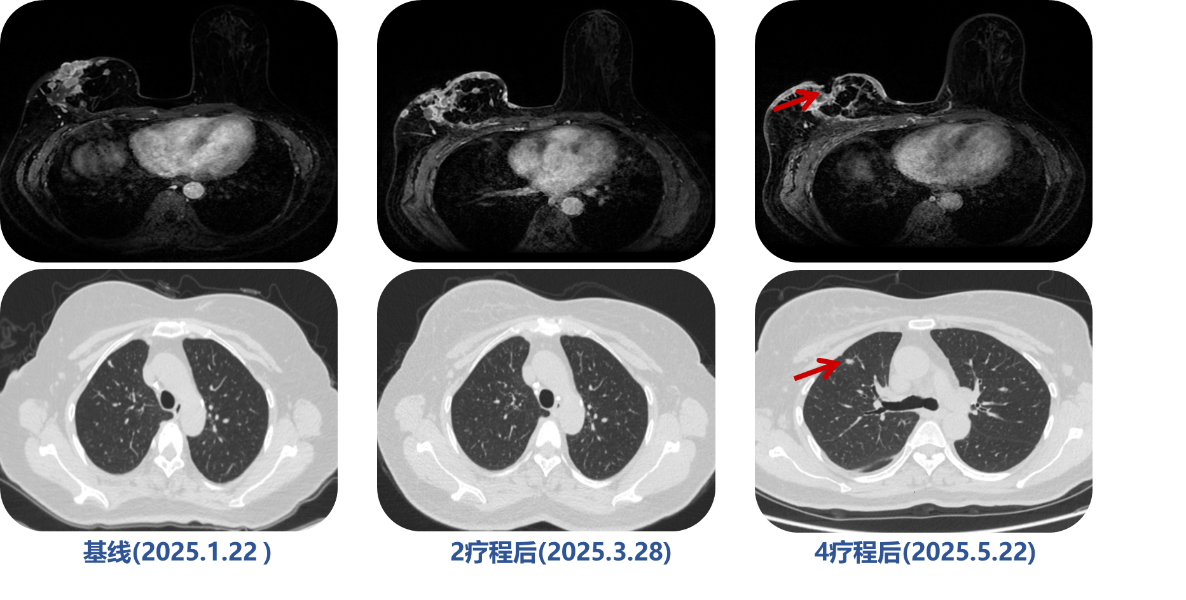

疾病进展 (2024.07.22):复查评估提示右乳病灶增大,侵犯皮肤,肺部出现新发病灶。

疾病进展 (2025.01.22): 评估显示右乳病灶再次增大并出现破溃。

疗效评估:治疗4周期,最佳疗效为疾病稳定(SD),但PFS仅3个月。

疾病进展 (2025.05.22):患者病情急剧恶化,右乳病灶破溃增大,皮下结节增多。

疗效评估(2025.7.22):治疗2疗程后,疗效评估为PR 。患者胸壁破溃病灶基本愈合,肺转移灶消失。